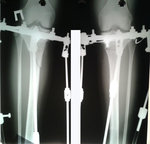

РЕНТГЕН ДО ОПЕРАЦИИ